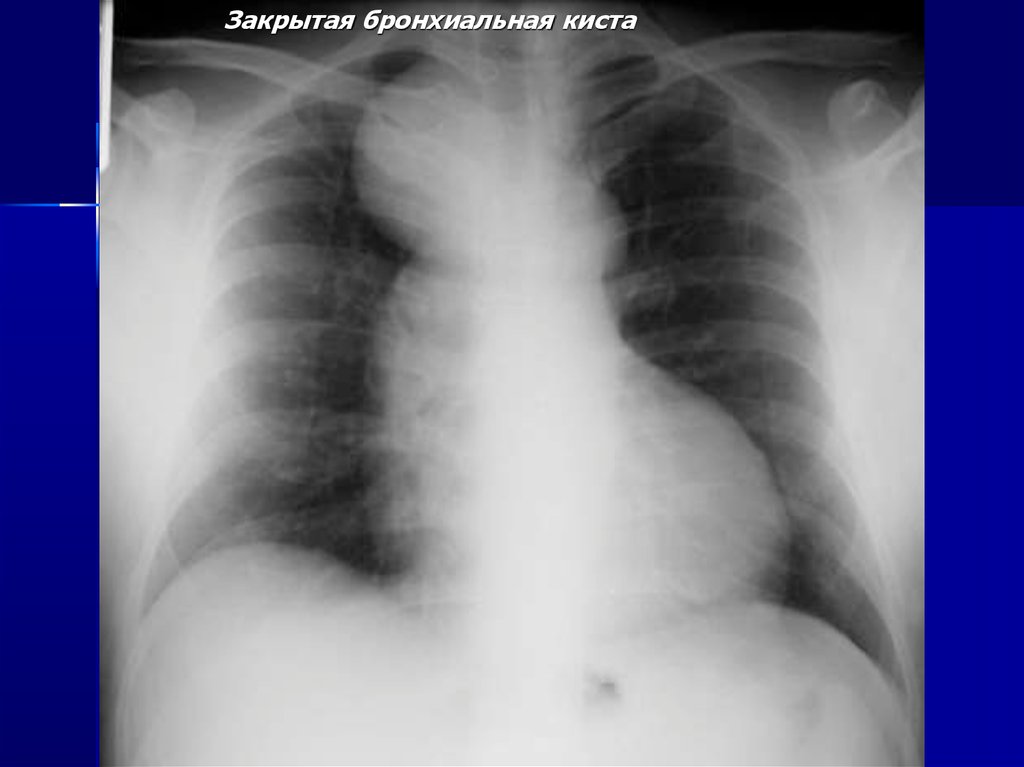

Закрытая бронхиальная киста